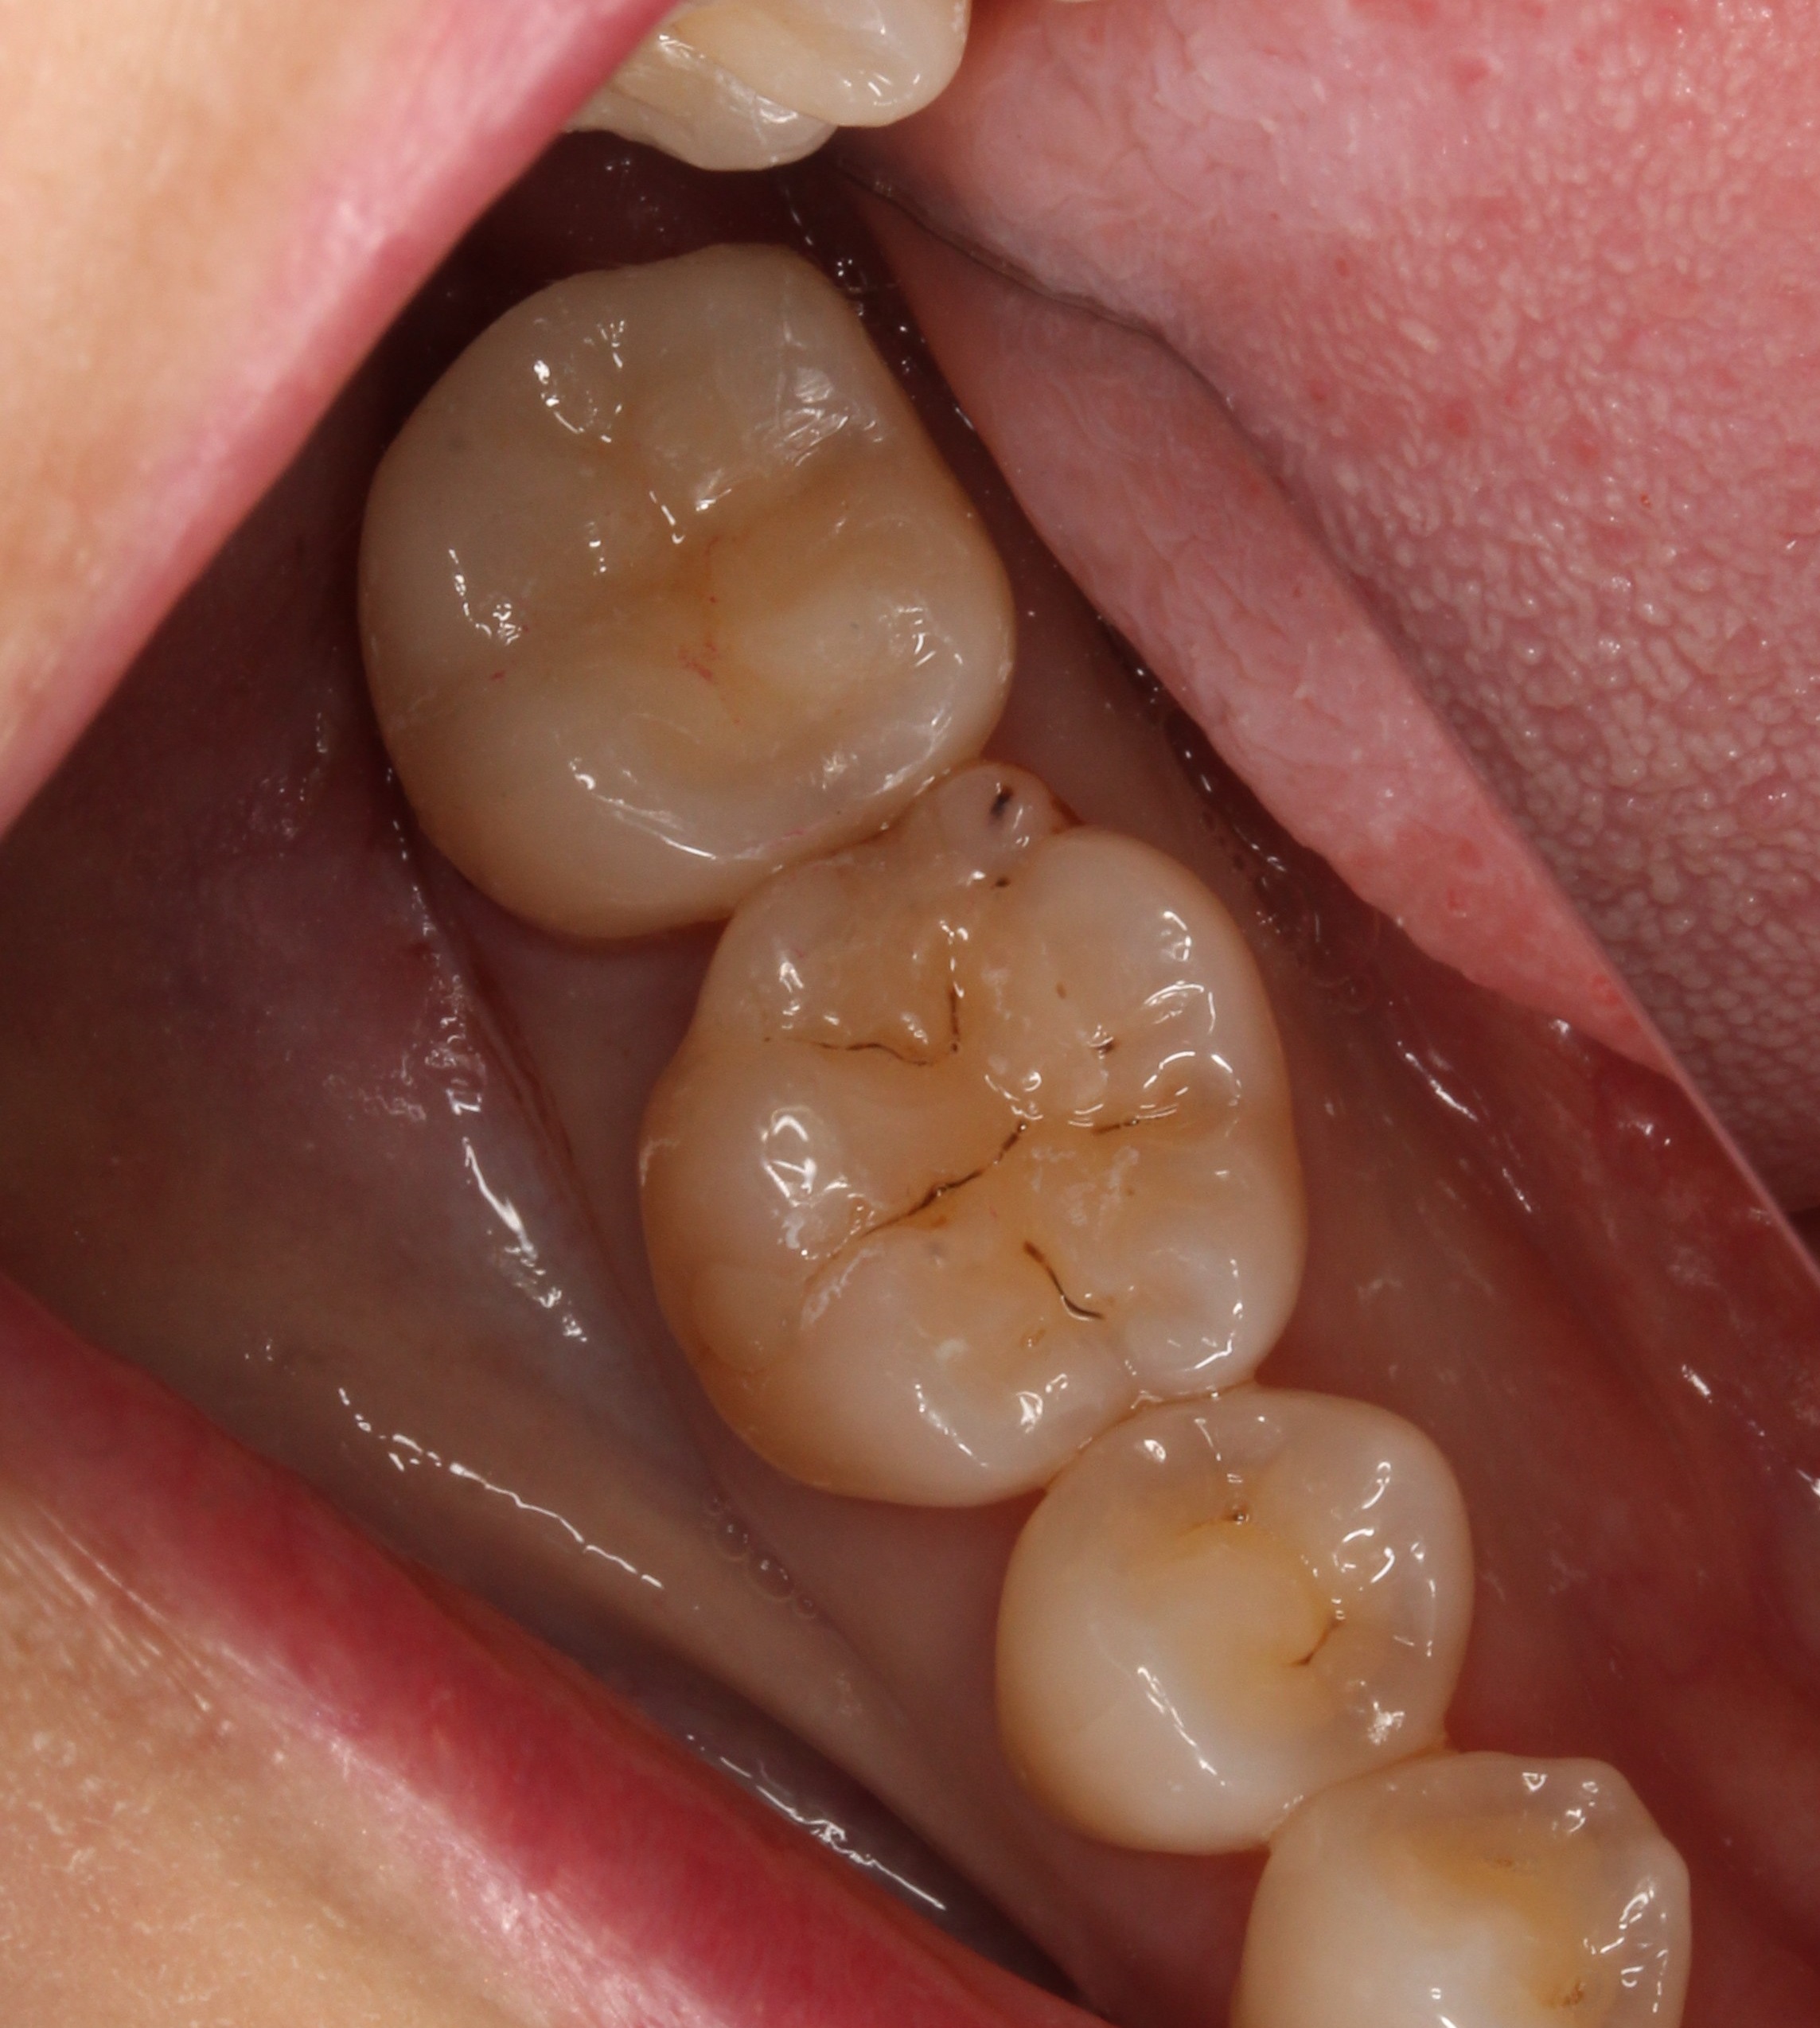

セラミックインレーがセットされた状態です。

治療した所が分からないくらい綺麗になりましたね(^^)/

これで治療が終わります。

お口の中を見てみると

どこを治療したか分からないですね。

セラミックも綺麗に安定しています。

無事治療が終わって良かったですね(*^-^*)